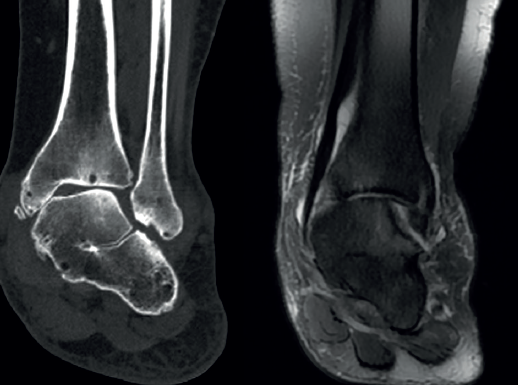

Con la llegada de pruebas avanzadas de imagen aumentó la estimación respecto a la población general. A partir de estudios con TC y disección en cadáveres se han publicado incidencias del 12-13%(29,30), cifras que son similares al 11% encontrado en un trabajo de coaliciones halladas en RM(31).

Sin un dato claro y con limitaciones sobre sesgos de selección reconocidos en muchos de esos trabajos, la bibliografía se ha decantado más por la predominancia de la CE, aunque quizás se deba a una mayor dificultad para reconocer una AC en las radiografías simples y en la RM(31).

Recientemente, se ha publicado un trabajo sobre incidencia en nuestro medio(38), con un total de 57 pacientes diagnosticados a lo largo de casi 13 años. Se reunieron 85 coaliciones en total, de las cuales un 61% fueron AC y un 37% eran CE. De todas las AC, la mayoría eran óseas (67%), pero en las CE casi todas eran fibrocartilaginosas (97%). Estas coaliciones no óseas formaban el subtipo más frecuente (57,6%) del total de las coaliciones encontradas.

Rozansky(41) y Lim(42) propusieron, solo para la coalición AC, una clasificación basada en imágenes 3D de TC. Ambos se basaron en la morfología de inclinación de la interlínea y la naturaleza del tejido (fibrocartilaginoso u óseo), pero Lim añadió la presencia de fractura con edema óseo asociando criterios de RM. Yun(43) también hizo uso de la TC y la RM para describir diferentes tipos de coalición AC según su localización y la presencia o no del os sustentaculi, que se sitúa entre el borde más posterior del sustentaculum tali y la prominencia más posteromedial del astrágalo. Por último, Wang(44) ha propuesto una excelente clasificación para describir la morfología de la coalición, según el hueso protagonista (sobrecrecimiento del astrágalo o del calcáneo, de ambos o con osículo intermedio), en función también de su condición fibrocartilaginosa u ósea, así como de la afectación sea de la subastragalina media, la posterior o de ambas.